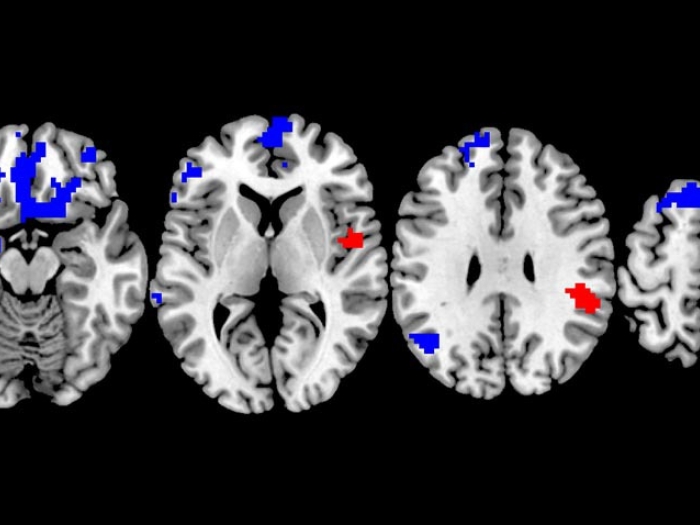

Brain scans of OCD.

Which OCD Treatment Works Best? New Brain Study Could Lead to More Personalized Choices

For people with OCD, or obsessive compulsive disorder, a new brain imaging study may help personalize treatment including exposure therapy.